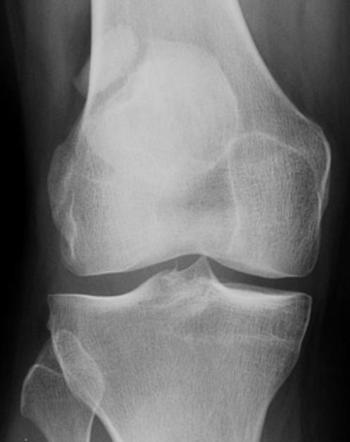

Bipartite Patella is usually diagnosed through a physical examination and imaging studies, such as X-rays, CT scans, or MRI scans. Doctors often look for any signs of separation in the kneecap and the presence of pain in the patellar region, especially during flexion and extension of the knee.